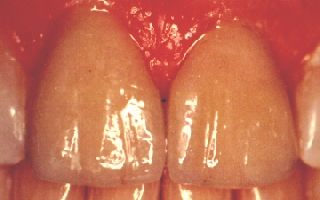

Twenty-Five Years Later!

This is a twenty-five year follow-up for the

patient in the pictures above. No maintenance was done to the

laminates other than brushing and flossing during all of those

years. As you can see, they look just as good as the day they

were placed. This shows the extreme durability and longevity

of porcelain laminate veneers. |